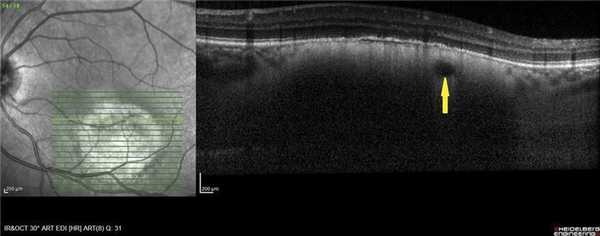

Между мембраной Бруха и патологическим очагом в 9 случаях была видна гипорефлективная линия, разделяющая базальную мембрану и Г.Х. Эту полосу «самоотграничения» зафиксировали преимущественно при высоте опухоли до 1,9 мм (6 глаз) (рис. 3). В 3 случаях проминенция составляла 2,3; 3 и 4 мм. Не исключено, что она соответствует пространству между мембраной Бруха и псевдокапсулой гемангиомы, которую практически всегда находят при гемангиомах орбиты.

Рис. 3. ОКТ-горизонтальный срез. Зона «самоотграничения» ГХ (указана стрелками).